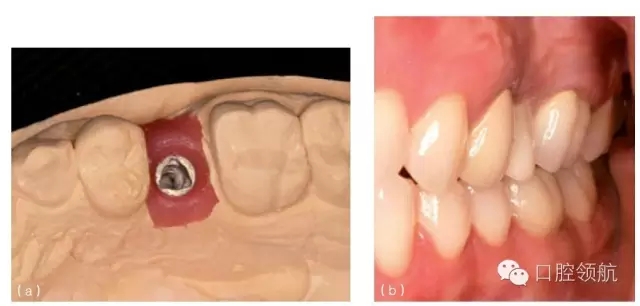

種植體植入時如果太偏舌側,會造成冠修復時,唇側頸部凸度異常(圖10.1b,圖10.27),或是冠的瓷層必須蓋過頰側軟組織以形成理想的頸部外形(圖10.28a~c)。這種覆蓋會使口腔衛(wèi)生的維護更困難,同時也會由于軟組織的根向退縮產(chǎn)生美學問題。在有的情況下,采用冠覆蓋頰側軟組織(圖10.29a~c)的設計也是必需的(類似于某些固定局部義齒的橋體),否則,冠將呈現(xiàn)出明顯的頸部缺損或外形凸度不足的情況(圖10.30a,b和圖31a,b)。

圖10.28 (a)種植體水平印模的模型。注意種植體位于近中稍偏舌側。(b)為改善頸部外觀,必須采用冠覆蓋頰側軟組織。(c)全冠要求大量的塑形,并且覆蓋軟組織,以獲得良好的美學效果。

圖10.29 (a)上頜第一前磨牙種植體位于鄰牙中部近舌側。(b)冠的牙合面觀,可見牙合面螺絲孔位于冠的舌側。(c)全冠的唇側觀,可見大量的烤瓷覆蓋軟組織。